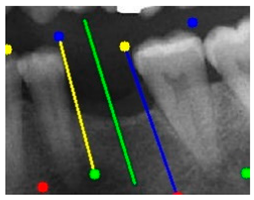

The angle bisector of the two auxiliary lines was then calculated using the angle bisector formula shown in (8), where (, , ) and (, , ) represent the coefficients of the two lines. The resulting internal angle bisector defines the preliminary implant pathway orientation derived by this framework. This bisector represents the most stable implant pathway orientation direction, ensuring that the implant avoids adjacent teeth and critical anatomical structures while maximizing bone–implant contact area. Such orientation enhances osseointegration stability and prevents complications from improper angulation, such as malocclusion or uneven stress distribution. The visualization of this process and the algorithmic design are presented in Figure 8. Finally, the auxiliary pathway generated by the algorithm was compared and overlapped with the implant pathway orientation annotated by dentists on the images to evaluate the predictive capability and accuracy of the model. The overlap results serve as a basis for further model optimization and provide valuable reference information for clinical application.

Figure 8.

Auxiliary lines are derived from adjacent teeth, the blue and yellow line is the result of implant pathway orientation visualization algorithm, and the green is the best implant pathway orientation.

3.3. Comparison with Clinical Ground Truth and AI-Assisted Framework

This subsection presents a comparison between the dentist-defined clinical gold standard and the predictions generated by our AI-assisted framework to evaluate the reliability of implant pathway orientation. The result is shown in Table 10, the preserved DPR validation set was used for verification, and the AI-assisted framework results were overlaid onto the original DPR images to provide a clear visualization. The AI-assisted framework pathways (green lines) were highly consistent with the dentists’ ground-truth annotations (black lines). Quantitatively, the mean squared error (MSE) between the predicted implant direction and the dentists’ planned results was only 1.537° across multiple test images. This minimal deviation validates the proposed system’s technical feasibility. It highlights its clinical potential to provide accurate and stable guidance for implant placement, thereby reducing the risk of misalignment and supporting efficient preoperative orientation.